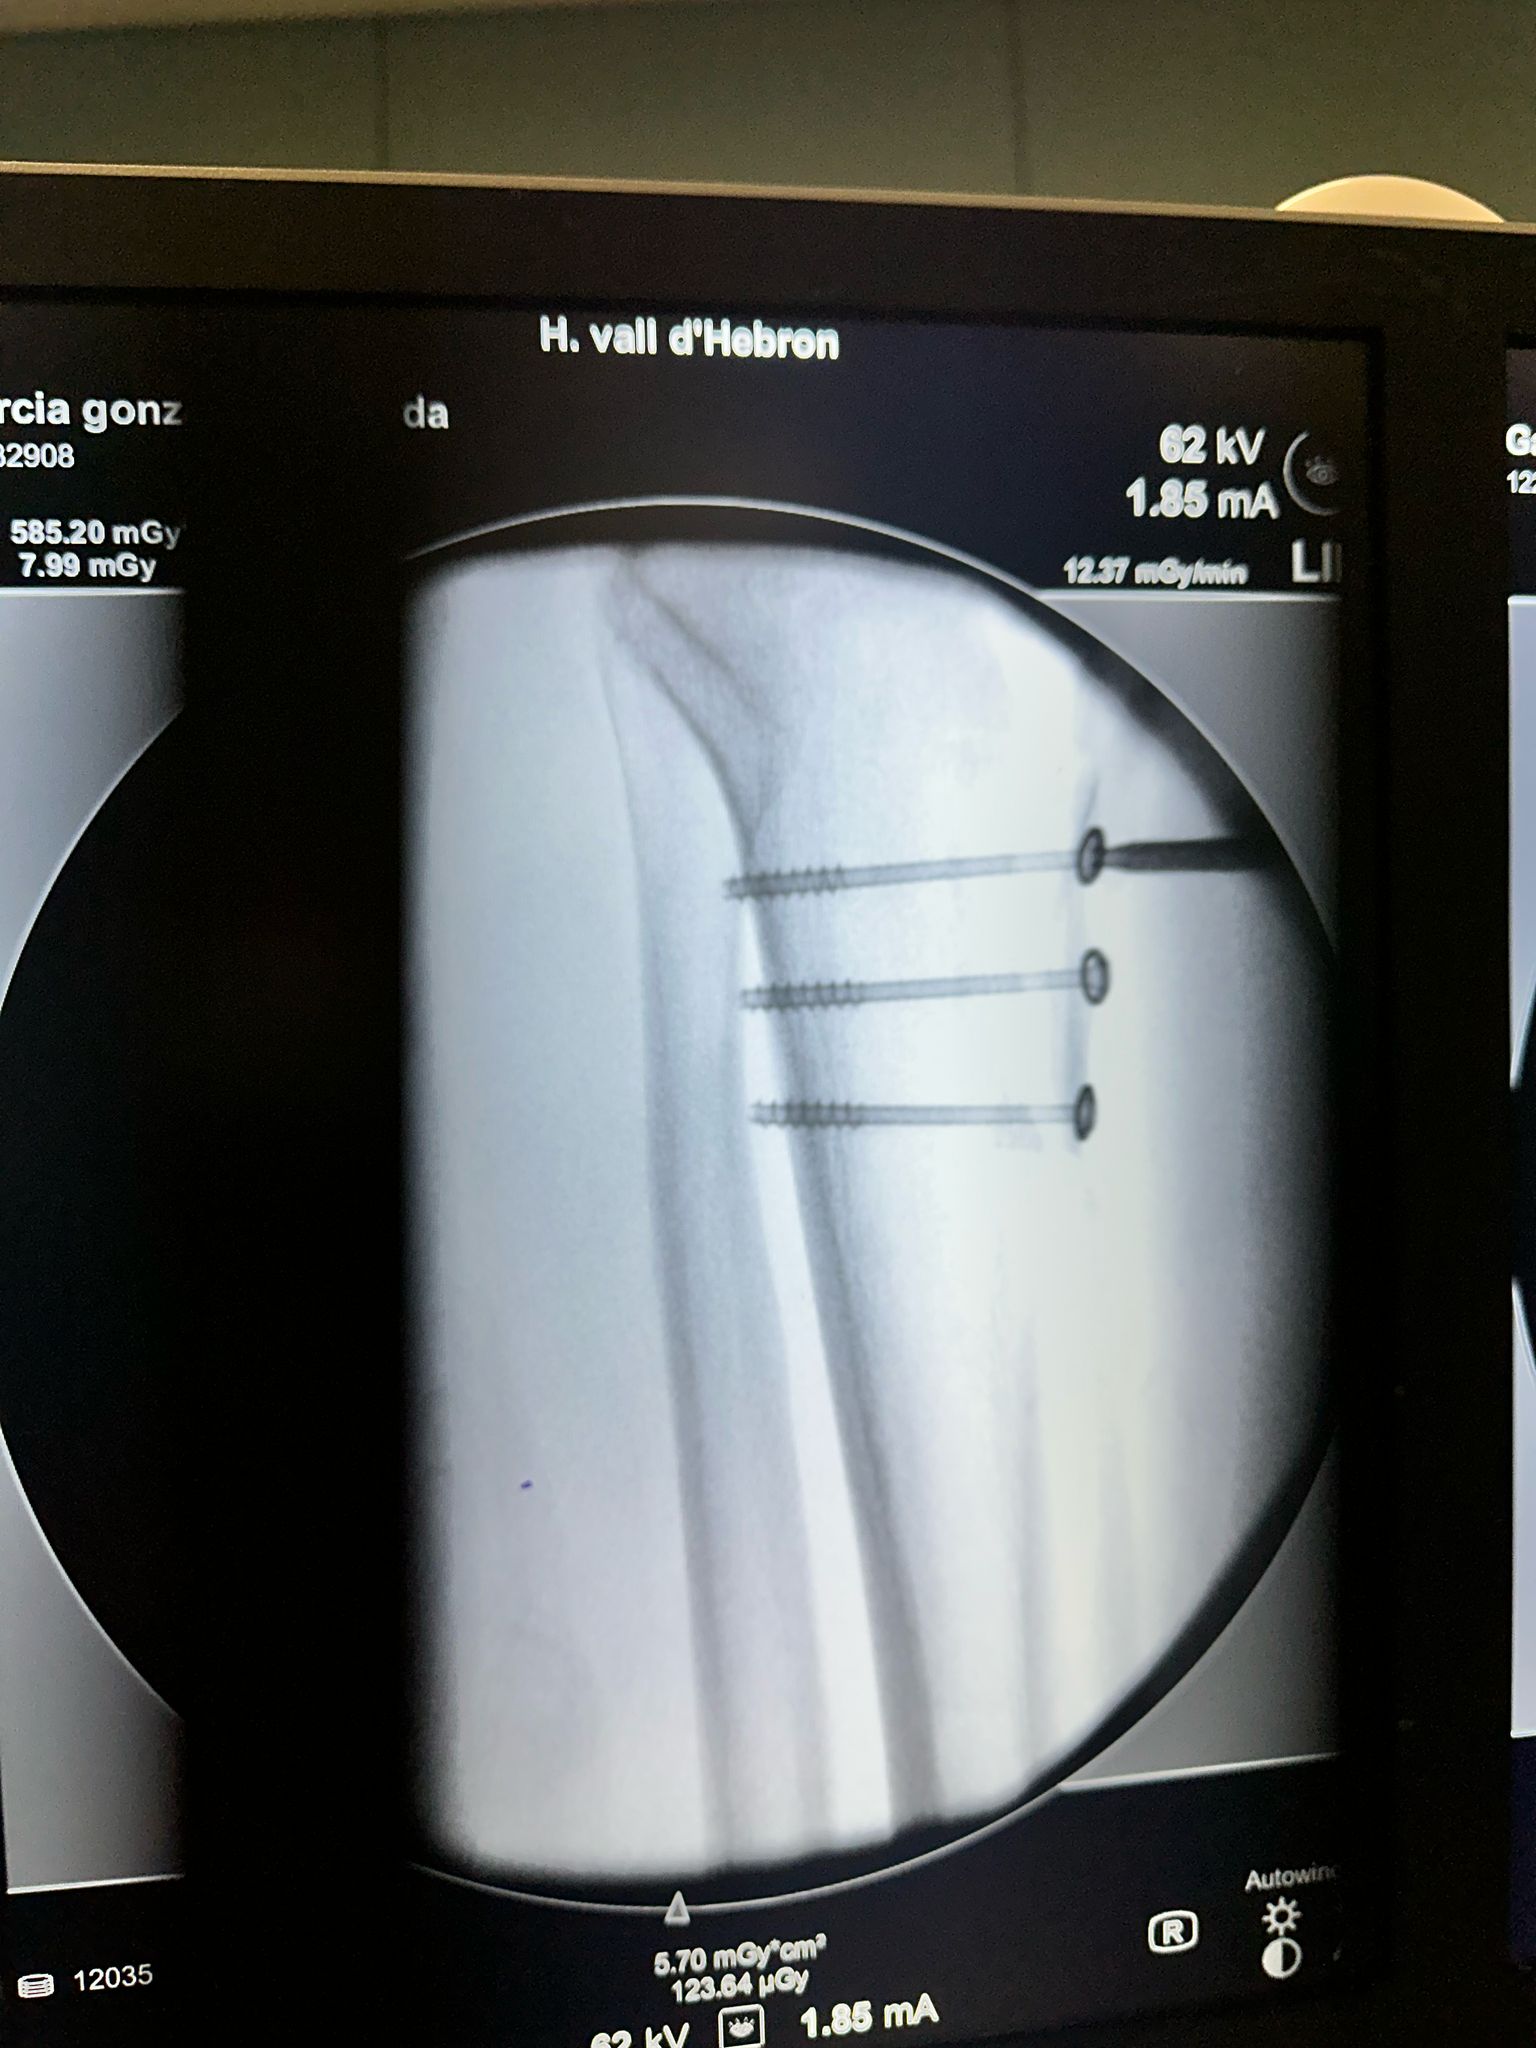

5. Fijación del injerto a la tibia con 3 tornillos.

Control radioscópico de osteosintesis con 3 tornillos